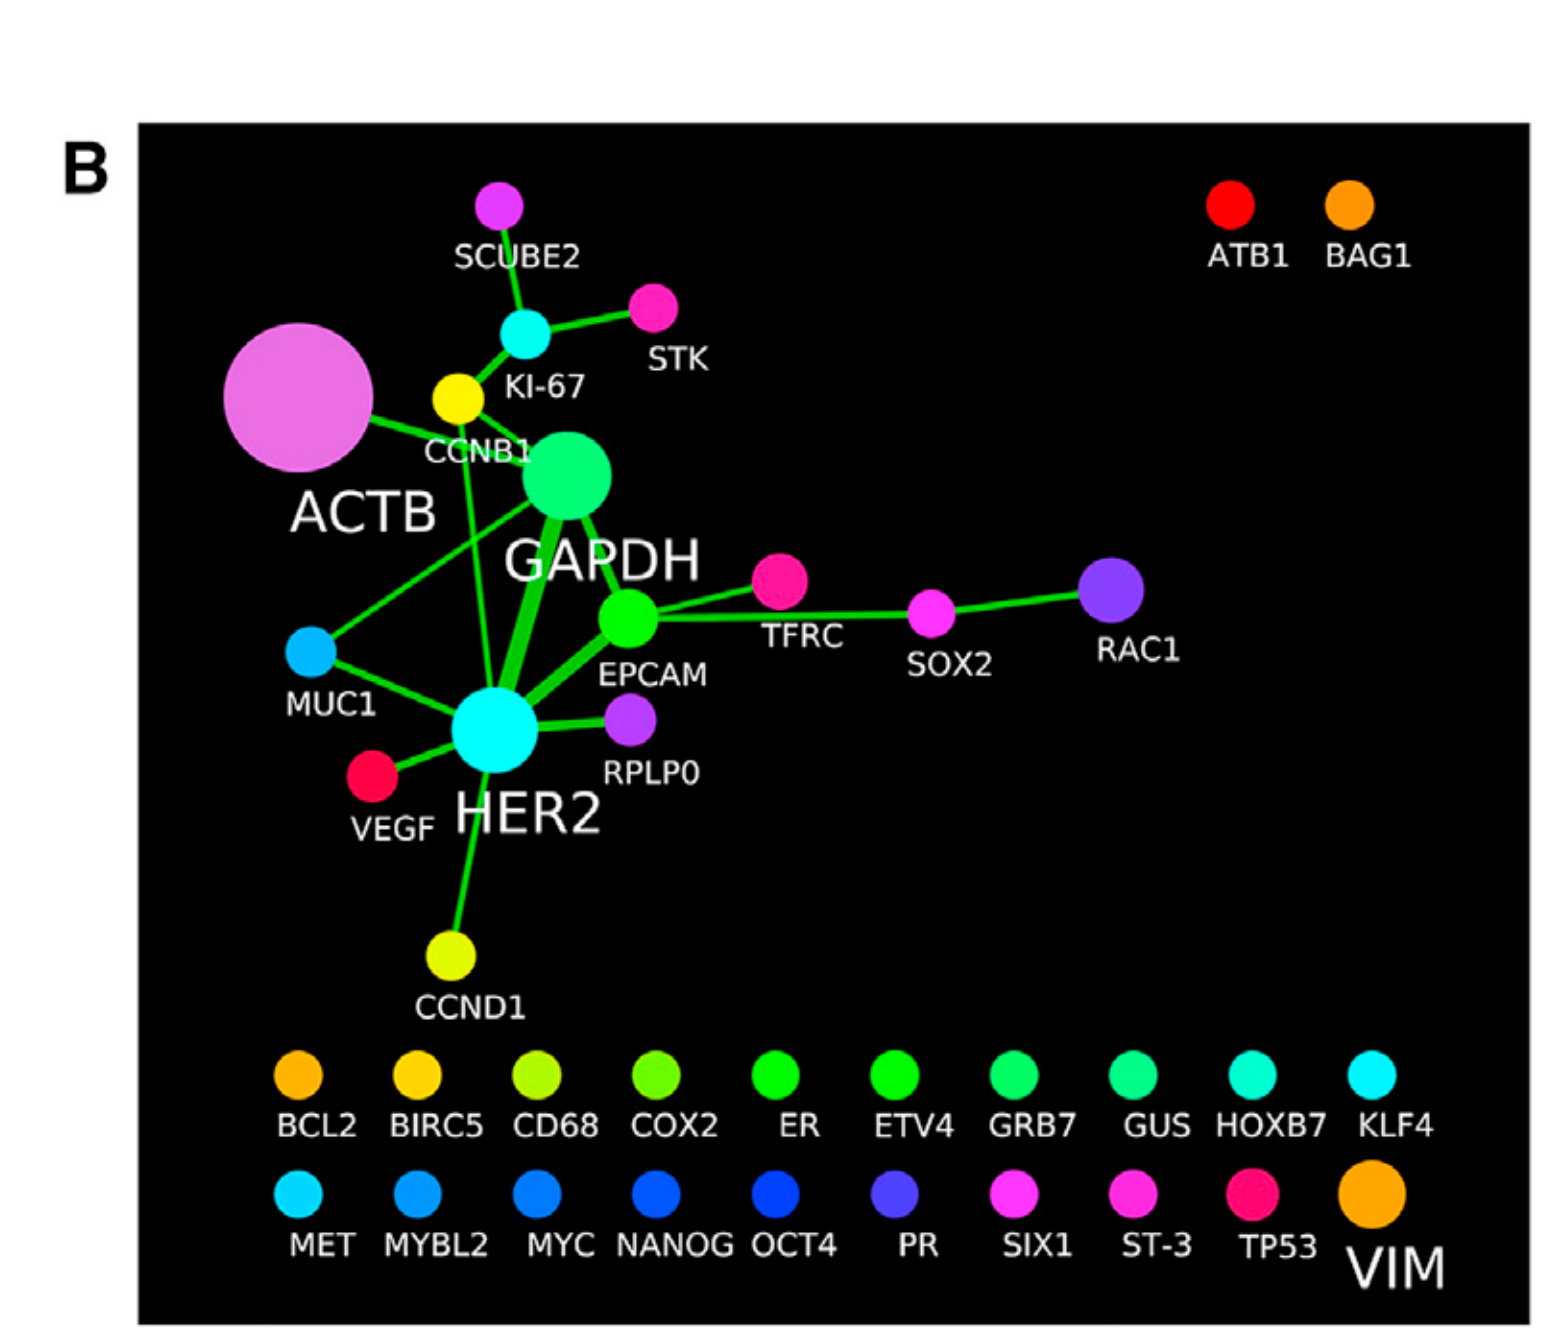

Li X. et al. - 2025

SPEX: A modular end-to-end platform for high-plex tissue spatial omics analysis

Proteomics

How does expression of a gene differ across patient categories?